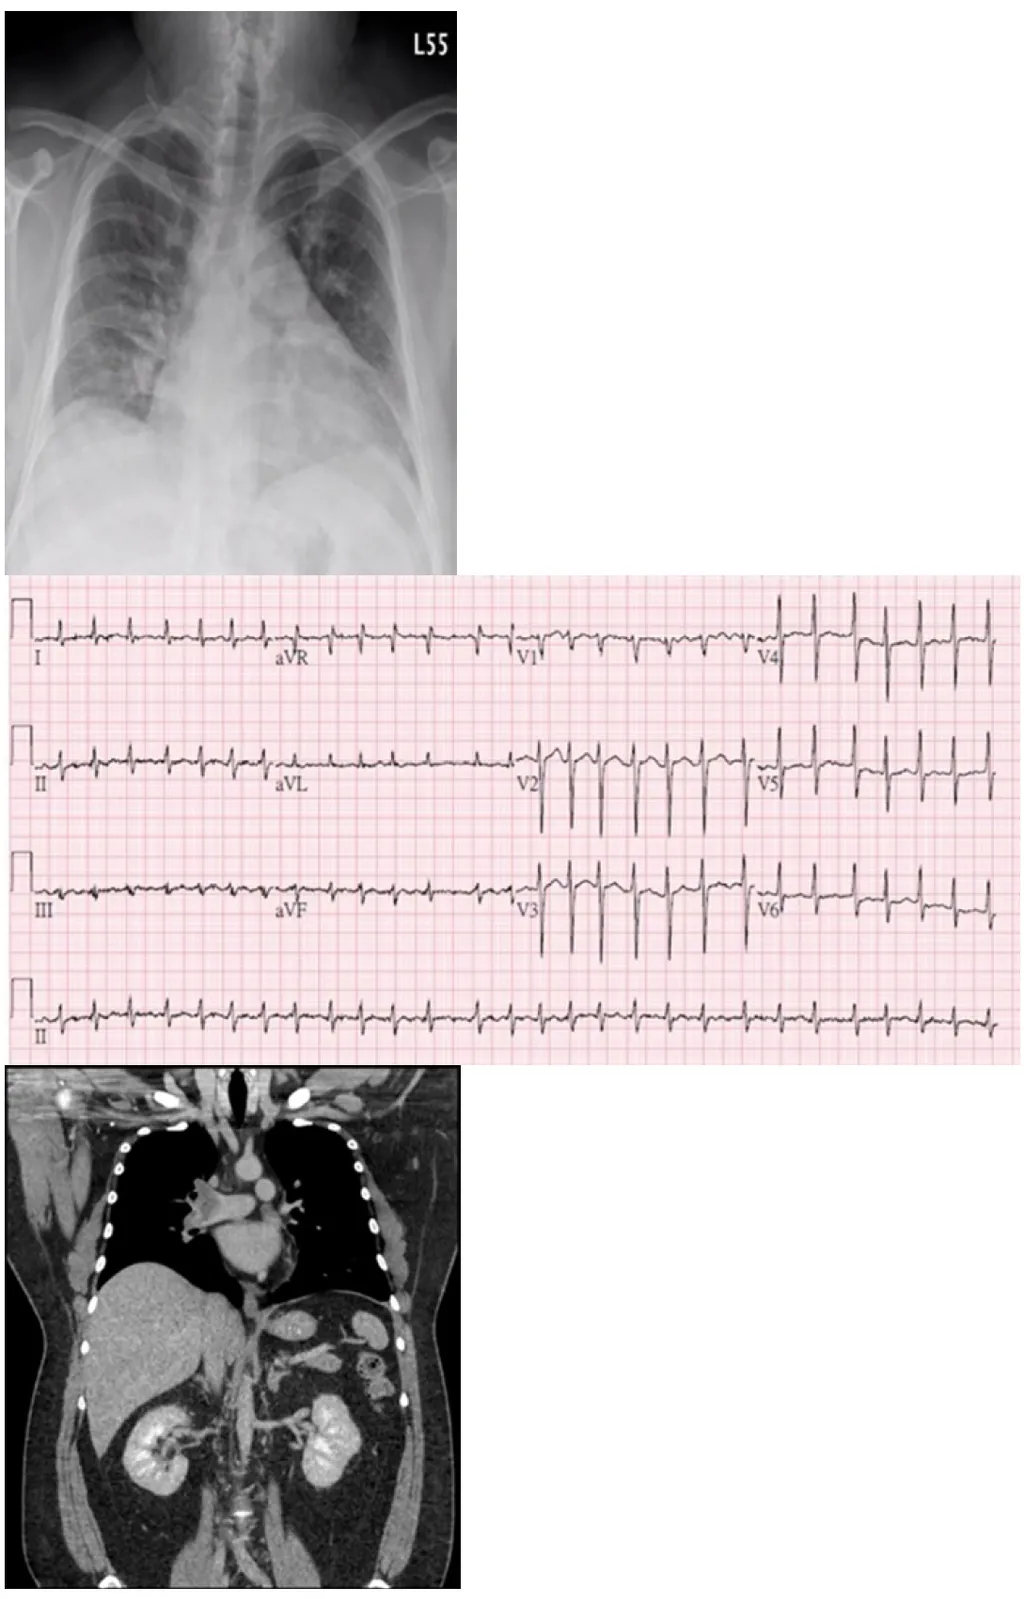

【115-1 醫學(三) 第9題】40 歲男性有 10 年心悸病史未妥善就醫,近一星期症狀加重,呼吸困難。到院時,BMI=41 kg/m , BP 126/72 mmHg,HR 141/min,RR 28/min,Temp 36.90 ℃,SpO2 97%,無貧血,甲狀腺觸診未有異常,未有第三心音及心雜音,肝脾不大,無腹水,雙下肢微腫。相關檢查如附圖。抽血報告如下:NT Pro-BNP 2470 pg/mL, Troponin T 0.019 ng/mL,D-dimer 20 mg/L FEU,ALT 196 U/L。下列何項診斷最符合目前狀況?